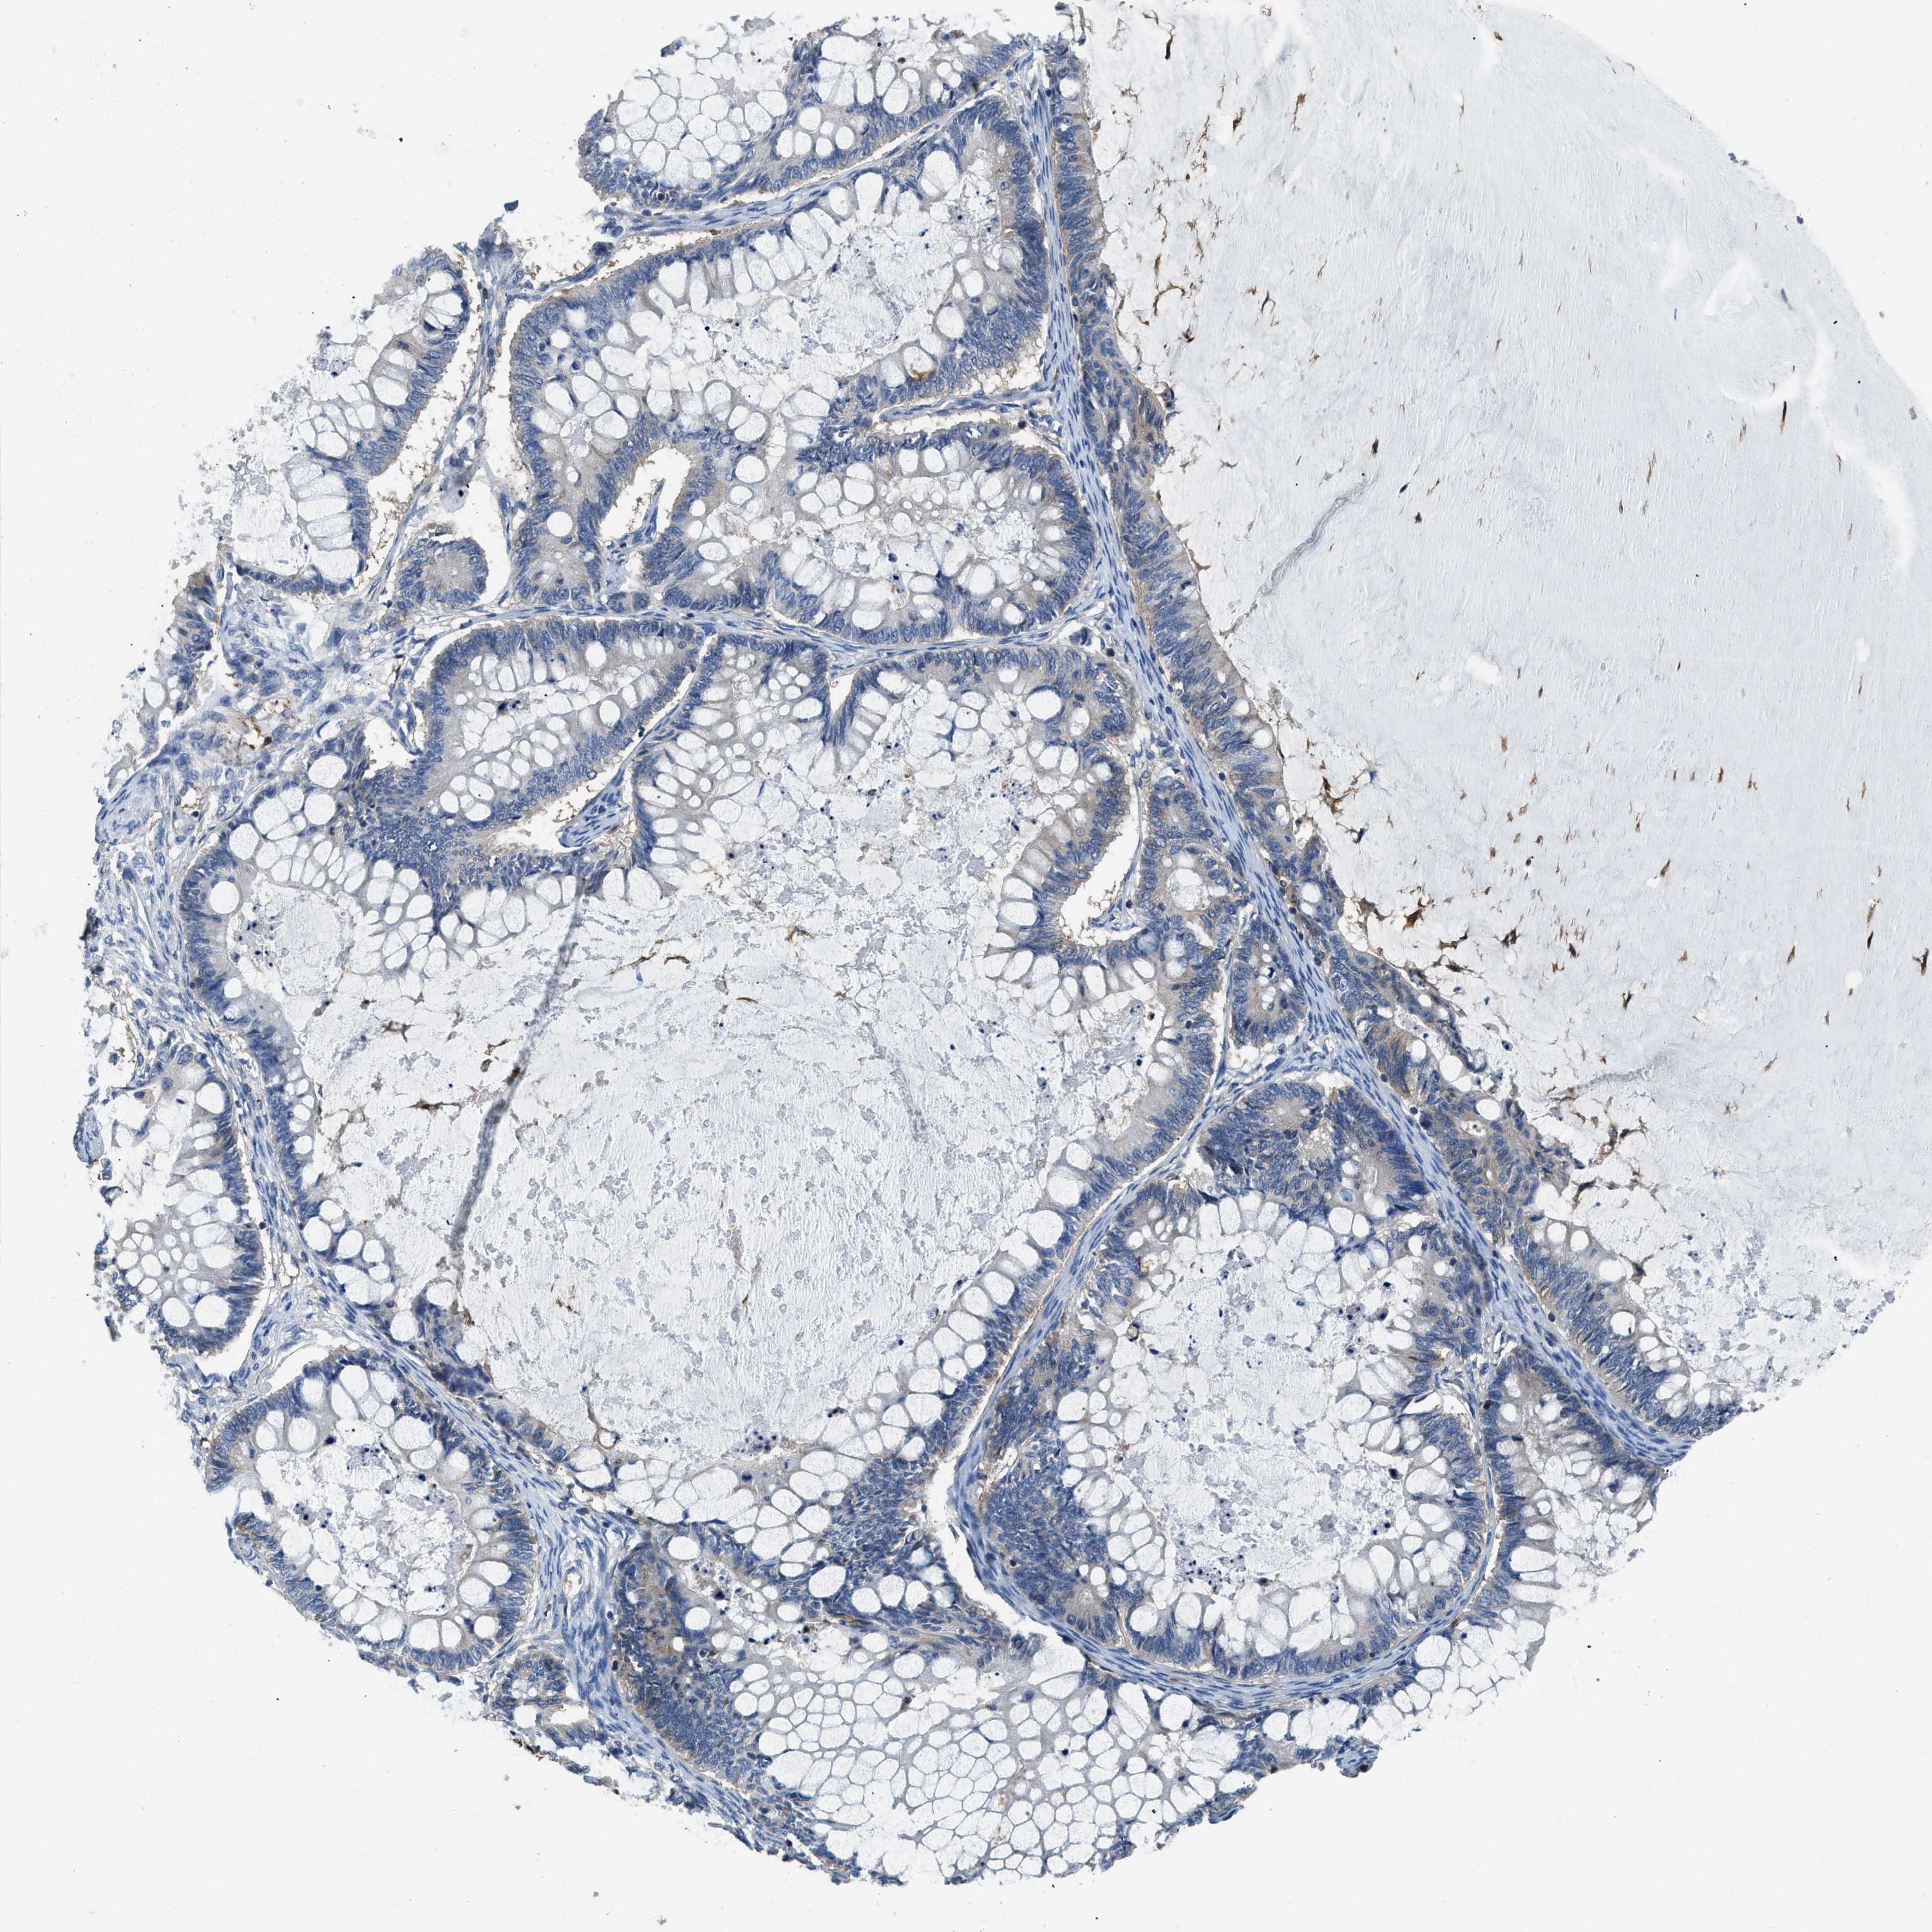

OVARIAN CANCER - Protein expressioni

A mouse-over function shows sample information and annotation data. Click on an image to view it in a full screen mode. Samples can be filtered based on level of antibody staining by selecting one or several of the following categories: high, medium, low and not detected. The assay and annotation is described here.

Note that samples used for immunohistochemistry by the Human Protein Atlas do not correspond to samples in the TCGA dataset.

Antibody stainingi

Antibody staining in the annotated cell types in the current human tissue is reported as not detected, low, medium, or high, based on conventional immunohistochemistry profiling in selected tissues. This score is based on the combination of the staining intensity and fraction of stained cells.

Each image is clickable and will lead to virtual microscopy that enables deeper exploration of all samples and also displays staining intensity scores, fraction scores and subcellular localization as well as patient and tissue information for each sample.

Antibody HPA029501

Antibody CAB019421

Cystadenocarcinoma, serous, NOS

Carcinoma, endometroid

Cystadenocarcinoma, mucinous, NOS

Carcinoma, NOS